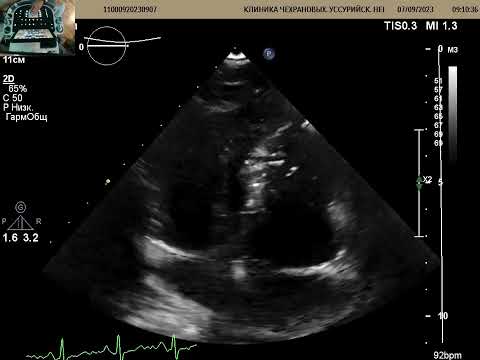

Будни врача УЗИ: пациент 65 лет. Направления нет, выписок из историй болезней нет. Со слов: инфаркты миокарда в 2005 и 2009. Операция в 2010: шунтирование, иссечение "аневризмы". Обследуется в связи с выявленным заболеванием легких ( онкология?). Акустическое окно: парастеранльный доступ - неудовлетворительное ( перекрыто легкими) ,апикальный доступ- неудовлетворительное, субкостальное окно- визуализация прям порадовала, знал бы что так будет- начал бы из этого доступа:( Описание: Комментарии: направления нет, выписок из историй болезни и амбулаторных карт нет! 1. Левый желудочек (1) ЛЖ значительно расширен, КДР 69 мм, Бипл.: КДО 209 мл , систолическая функция значительно снижена, КСО 158, ФВ 24%; (2) Стенки ЛЖ: МЖП: базальный и средний отделы 8-10 мм, верхушка- истончена 3-4 мм, движение низкоамплитудное, лоцируется на всем протяжении, шунтов не выявлено; - ЗСЛЖ - 8,1 не утолщена, движение низкоамплитиудное; (3) Зоны нарушения кинеза миокарда - аневрзима верхушки, легкий гипокинез боковой стенки, гипокинез задней, нижней, нижне и передне-септальной стенок пер. пер.-септ. септ. нижн. задн. бок. базальные 2 2 2 2 2 1,5 средние 2 2 2 2 2 1,5 верхушечные 5 5 5 5 1-норма 2 гипокинез 3 акинез 4 дискинез 5 аневризма 99 - невидим. (4) Диастолическая функция ЛЖ нарушена по 1 типу 2. Правый желудочек -(1) Нормальные размеры и систолическая функция ПЖ ;(2) Нормальная толщина стенок ПЖ 3. Предсердия: левое предсердие значительно расширено, ЛП 49 мм , индекс ЛП 51 мл/м2 правое - не расширено межпредсердная перегородка лоцируется на всем протяжении, транссептальных потоков не выявлено, 4. Клапанный аппарат (1) МК - створки уплотнены, движение створок дискордантное, раскрытие достаточное, МR легкая -(2) ТК - не изменен, движение створок дискордантное, раскрытие достаточное, TR легкая -(3) АК - створки уплотнены, открытие не ограничено, скорость нормальная, AR минимальная (4) ПК не изменен, PR легкая 5. Магистральные сосуды: аорта: незначительно расширена в восходящем отделе 39 мм, кровоток нормальный; легочный ствол не расширен, дополнительных потоков не выявлено 6. Перикардиальный выпот: нет; 7. Новообразования, вегетации: нет; 8. НПВ не расширена, коллабирует более 50% (RAP 3 mmHg), СДЛА 25 мм.рт.ст. Заключение: Выраженная дилатация левого желудочка ,КДР 69 мм, КДО 209 мл. Выраженная систолическая дисфункция левого желудочка , ФВ ЛЖ 24%. Состояние после пластики аневризмы ЛЖ. Тотальный гипокинез стенок ЛЖ за исключением боковой стенки ( легкий гипокинез). Диастолическая дисфункция ЛЖ, тип 1. Значительная дилатация левого предсердия.ЛП 49 мм , индекс ЛП 51 мл/м2 Уплотнение створок аортального и митрального клапанов. Минимальная аортальная регургитация. Незначительная дилатация восходящей аорты 39 мм.